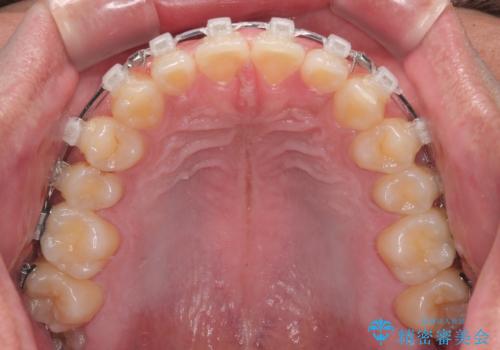

- クリアブラケット

- 1年7ヶ月

- 10-30回

- 上下前歯の隙間を気にして来院された患者様です。

飲み込みや話をするときに舌を突出させる癖が強くあり、それが原因でスペースが空いていました。

舌癖を改善するためのトレーニングを行いながら、ワイヤー装置を用いて前歯の隙間を閉じていくこととしました。